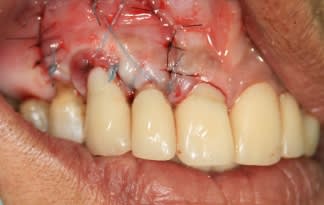

.. attendez la maturation des tissus avant de le descendre, quand mème.

gulguch à raison, il semble qu'il y ait un très léger mieux.

La vitalité, le bourgeonnement, la vascularité à 10 jours me semblent satisfaisant.

néanmoins permet moi de douter du réel intérêt de cette intervention...certes, on a l'impression qu'il y a plus de volume, mais on est encore en période inflammatoire...donc prudence...

Il est effectivement bien trop tôt pour pouvoir dire quoi que ce soit. Mais je crois que tu obtiendra une amélioration en regard de 13.

Pour être un peu critique par rapport à ton cas, je dirais que tu aurais pu améliorer la traction de ton lambeau par l'utilisation de sutures plus adaptées (sutures suspendues, ...)

Christophe, ce n'est nullement une critique mais une constatation et si celà a été perçu comme telle je m'en excuse. En regardant ton tissu gingival avant et aprés l'intervention il me semble qu'il est le même, par ailleurs pluton a une remarque pertinente tu es en phase inflammatoire et les tissus ne sont pas encore stables. Je souhaite vivement voir la photo à 15 jours et à 1 mois et surtout que ta greffe fonctionne.